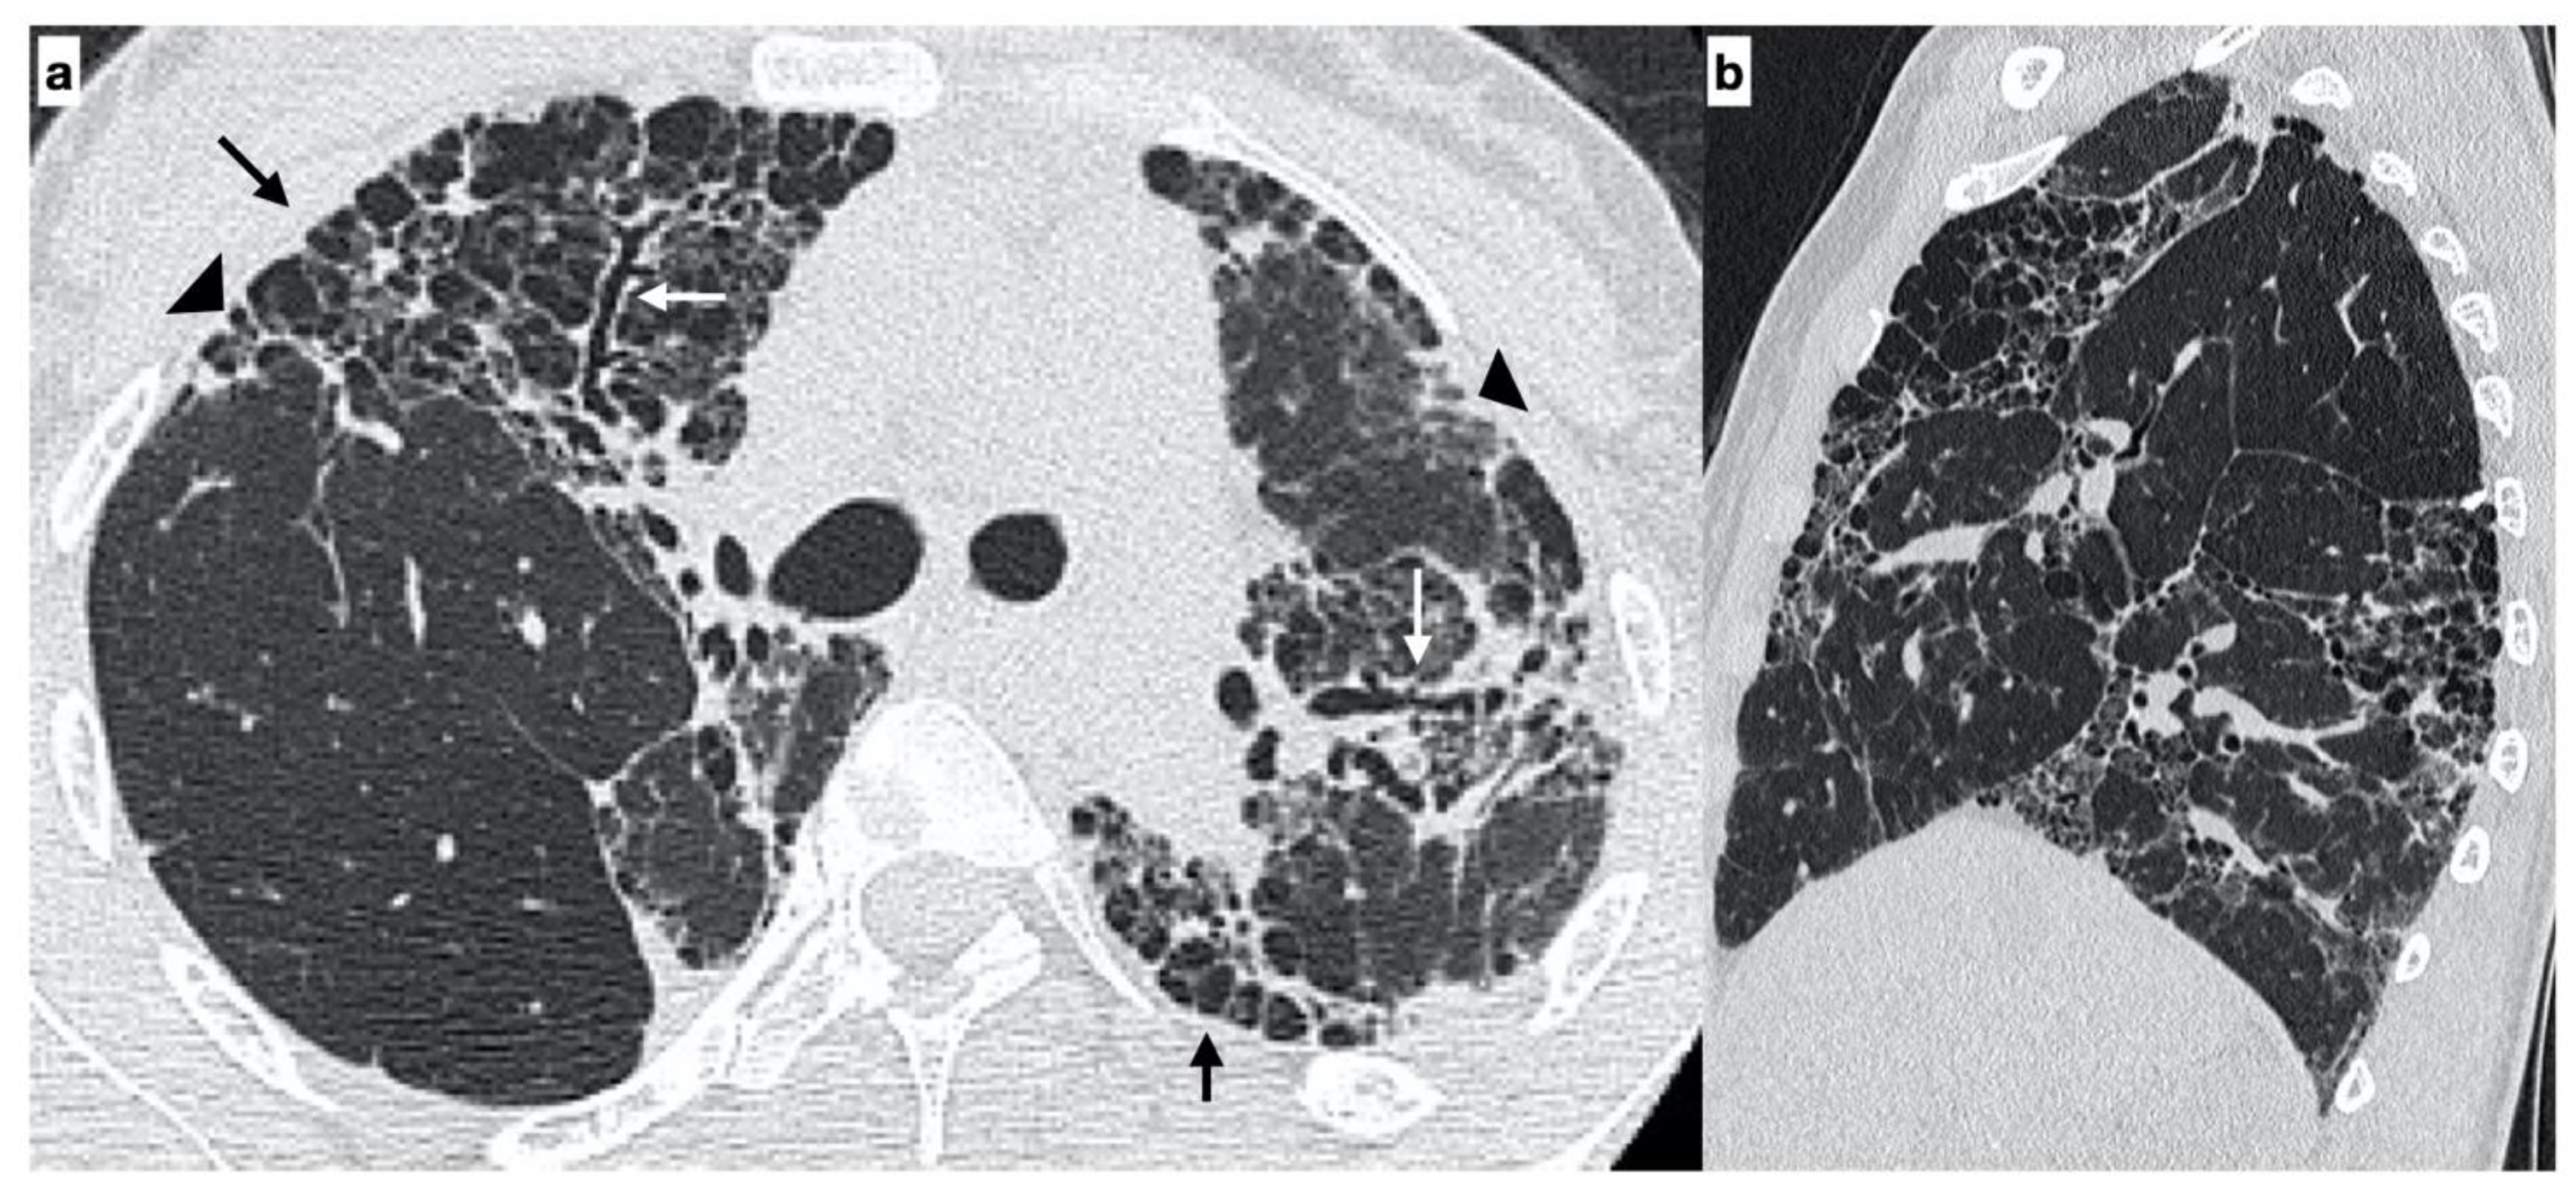

2.2. High-Resolution Computed Tomography

- Usual interstitial pneumonia (UIP): the presence of honeycombing in association with a reticular pattern with or without traction bronchiectasis/bronchiolectasis, with a subpleural and basal predominance;

- Probable UIP: the presence of a reticular pattern in association with traction bronchiectasis/bronchiolectasis without honeycombing and with a subpleural and basal predominance;

- Indeterminate UIP: the presence of subtle reticulation or ground-glass opacities, with a subpleural and basal predominance;